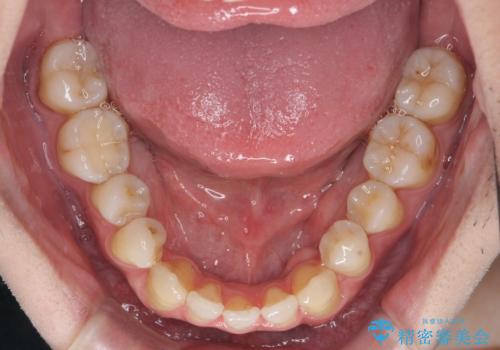

インビザラインでの臼歯の反対咬合の治療は難しいことが多いです。

今回は下の前歯を1本抜くことで、下の奥歯をしっかり内側に傾けて治療を行いました。